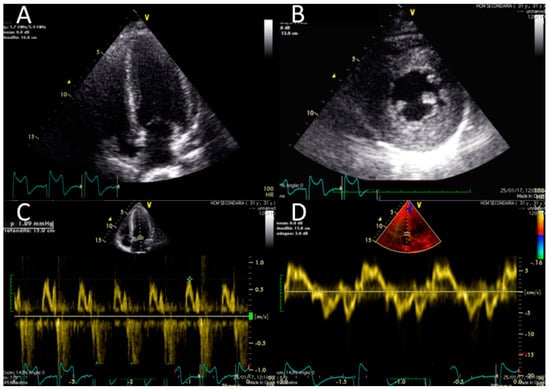

Electrocardiography suggested cardiac hypertrophy, confirmed at cardiac ultrasound, organised in the context of evaluations for kidney transplantation, which disclosed signs of relevant cardiac hypertrophy, out of proportion with her mild hypertension, confirmed at cardiac magnetic resonance (Figure 2, Figure 3 and Figure 4).

Figure 3. Echocardiographic findings. Echocardiographic findings show a moderate increase in LV thickness (max diameter 17 mm inferior and inferoseptal walls) in a four-chamber view (panel A) and on the mid short axis (panel B). Slightly reduced longitudinal function (S wave 0.07 cm/s) (D) and no significant abnormality of diastolic function (normal E/A pattern and E/E′ 10) were found (panel C and D) (Video S1 and Video S2).